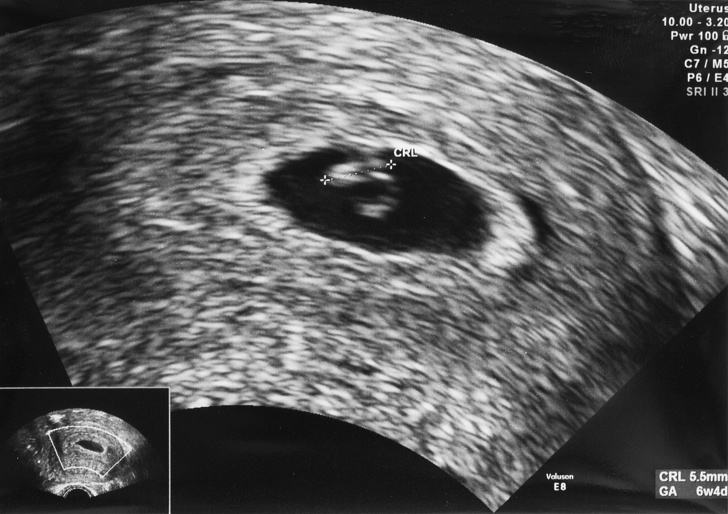

Ми прилетіли з чоловіком в інше місто, де нас зустріла сімейна пара. Їм було важливо познайомитися з нами обома. Ми вирішили поспілкуватися в одному з кафе. Спочатку було трохи ніяково, адже стільки питань треба обговорити при першій зустрічі, а тема дуже делікатна. Але все пройшло добре. Як тільки формальності зважилися, ми поїхали в клініку. Там нас зустріла завідуюча відділенням. Виявилося, що вона наш репродуктолог. Лікар подивилася всі мої аналізи, зробила мені УЗД, і їй все сподобалося. Я була така щаслива — це непередаване відчуття, що ти здатний врятувати чиєсь життя.

Важливо розуміти, що сурогатне материнство не все залежить від самої сурогатної матері. Наприклад, в моєму випадку у биоматери взяли яйцеклітини і «зробили» ембріони, щоправда, вийшло їх зовсім небагато — всього 6 яйцеклітин, і з них тільки 5 ембріонів. Потім ці ембріони проходять генетичний розвиток, в результаті якого вийшло лише 2 ембріона нормальної якості.